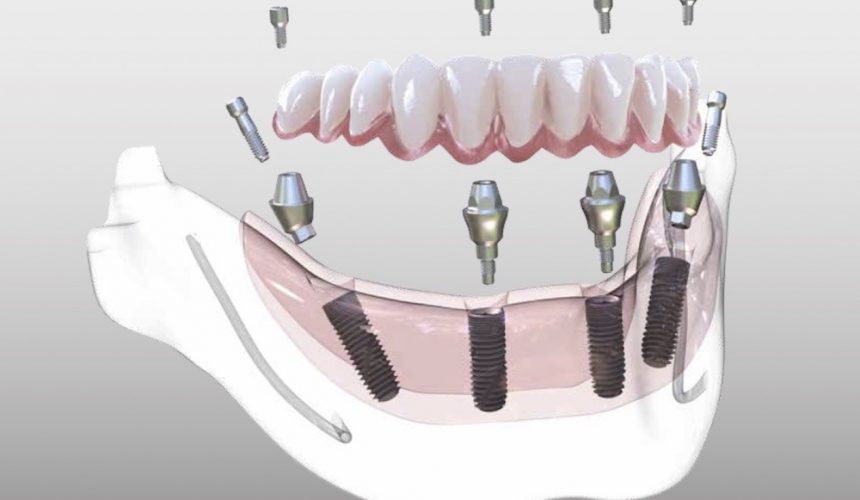

Пошаговое руководство по установке съёмного протеза на импланты